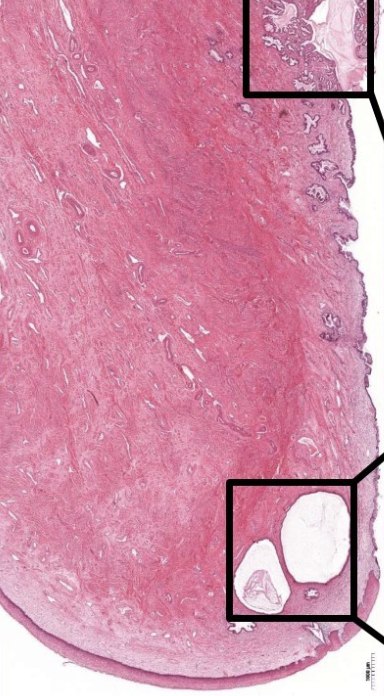

label this slide

cervix

what is this

epithelial cyst

transformation zone

endocervix to exocervix transformation, towards stratified squamous non keratinized epithelium